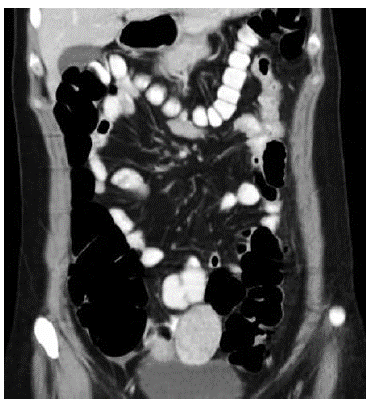

Taking the patient's stability and absence of peritoneal irritation into account, we chose a conservative approach and started intravenous fluid therapy, analgesics, gastric protection, antibiotics (piperacillintazobactam). Abdominal CT showed alteration of mesenteric fat tissue around the distal third of the descending colon and the proximal sigmoid, as well as adjacent air levels indicating pneumoperitoneum around the left hepatic lobe and para-colic mesenteric air (Figures 3 and 4).